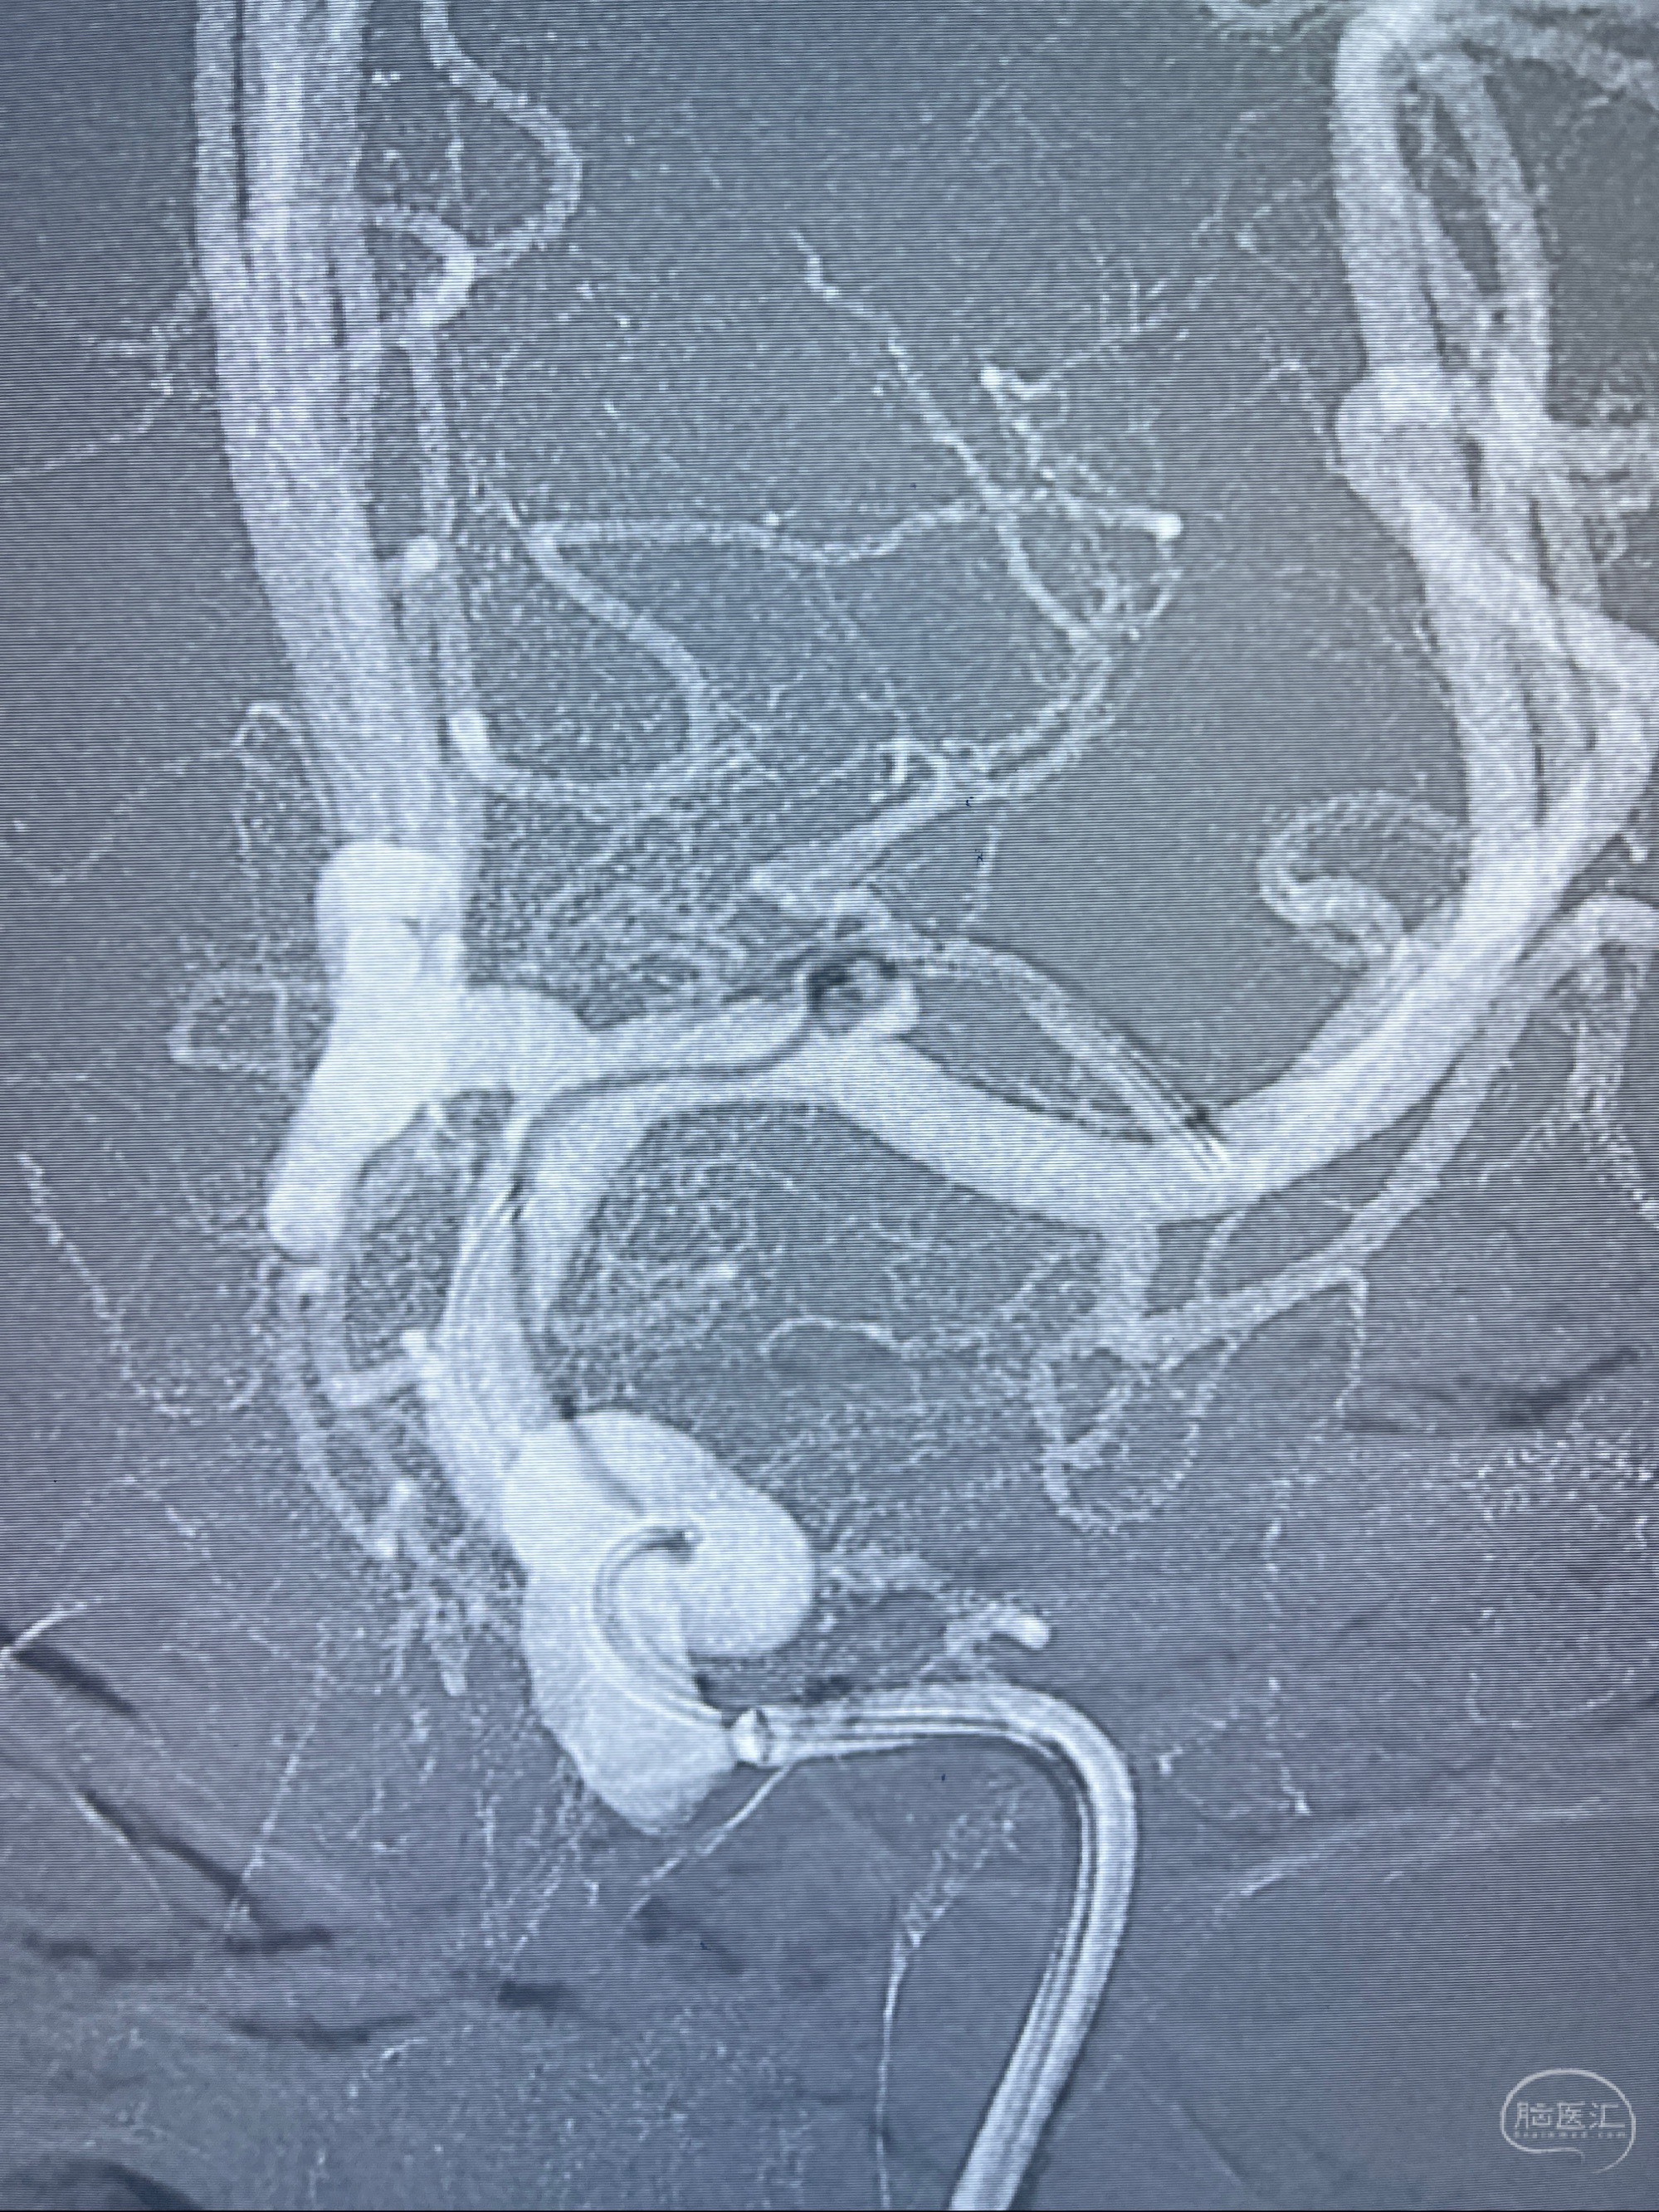

2023-08-14DSA:

左侧大脑中动脉动脉瘤,约2.6-2.8-3.4-2mm大小(瘤颈部、瘤体部、瘤高)

1.左侧大脑中动脉动脉瘤,约2.6-2.8-3.4-2mm大小(瘤颈部、瘤体部、瘤高)

2.外科手术夹闭or介入支架辅助栓塞